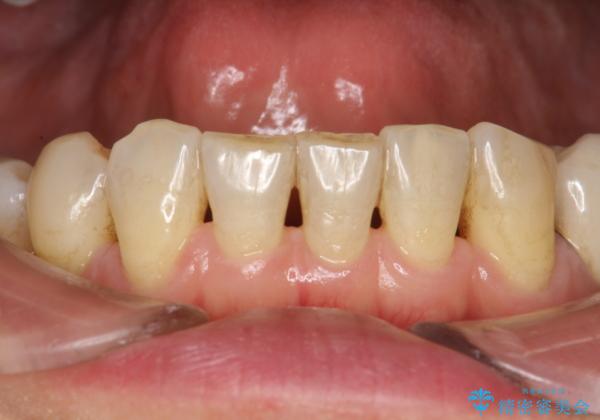

PMTCでオーラルケア

- 定期的にメンテナンスにいらしている方です。特にお変わりないとのことでPMTC60分コースで全体的なクリーニングを行いました。

オーラルケアをしっかりと行うことで、きれいな口もとだけでなく、全身の健康にもつながります。

治療せず放置してある歯周病は、口の中で細菌を培養しているのと同じことです。歯周組織が大きく壊れてしまう前に初期の炎症を止め、口と体の健康を維持できることが大切です。

- 歯を白くする目的の施術ではありません